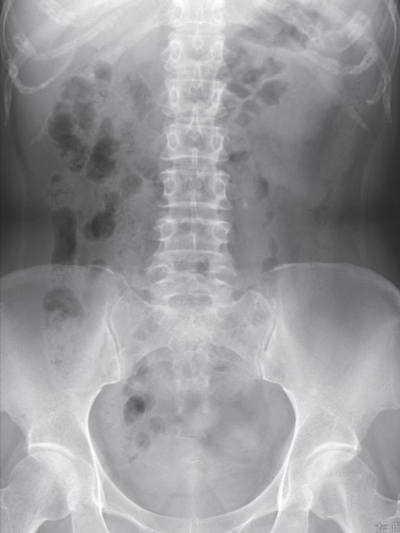

尿所見:蛋白(−)、糖(−)、ケトン体(−)、潜血+、沈渣に赤血球 10~19/HPF、白血球 1~4/HPFを認める。血液所見:赤血球434万、Hb 13.8 g/dL、Ht 42%、白血球 9,600、血小板 21万。血液生化学所見:総蛋白 7.0 g/dL、アルブミン3.8 g/dL、総ビリルビン 0.9 mg/dL、AST 30 U/L、ALT 28 U/L、LD 179 U/L(基準 120~245)、尿素窒素 20 mg/dL、クレアチニン 1.0 mg/dL、尿酸 6.6 mg/dL、血糖 98 mg/dL、Na 139 mEq/L、K 4.2 mEq/L、Cl 98 mEq/L、Ca 9.1 mg/dL。腹部エックス線写真(臥位)を別に示す。